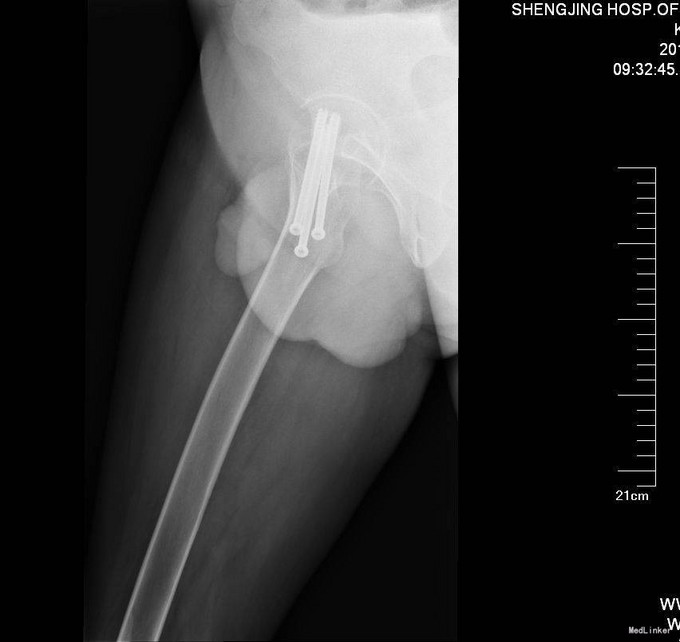

患者入院后完善相关检查,患者未满65周岁,所以择期行右股骨颈骨折闭合复位空心钉内固定术,术后患者3天后出院。